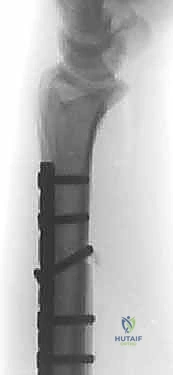

الخطوة 4: التثبيت الديناميكي (Dynamic Compression)

بعد إزالة الجزء الزائد، يتم تقريب طرفي العظم المقطوعين معاً. هنا تبرز مهارة الجراح؛ حيث يستخدم الدكتور هطيف شريحة معدنية متخصصة (Dynamic Compression Plate) ومسامير من التيتانيوم لتثبيت العظم بقوة. هذه الشريحة مصممة لضغط نهايات العظم معاً، مما يحفز الخلايا العظمية على الالتئام السريع.